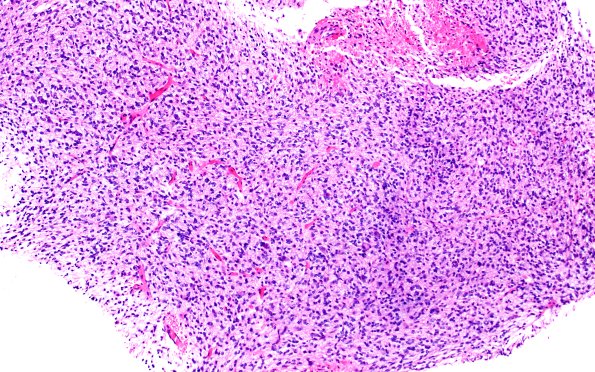

Washington University Experience | NEOPLASMS (GLIAL) | Diffuse midline glioma, H3 K27-altered | 16B1 DMG (Case 16) H&E 10X

16B1-4 H&E-stained sections show small fragments of brain parenchyma infiltrated by a markedly hypercellular glioma. The tumor is composed of mildly pleomorphic cells with indistinct cytoplasmic borders and scant amounts of eosinophilic cytoplasm. The cells have round to ovoid nuclei with mild atypia, fine chromatin, and micronucleoli in a subset. Mitoses are increased, and scattered karyorrhectic debris is present. Microvascular proliferation and necrosis are not appreciated in this limited sample. (H&E)